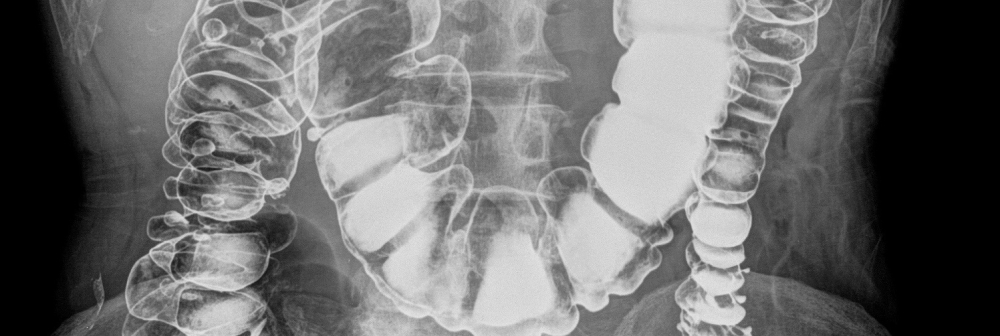

A fluoroscopy unit uses x-rays and an Image Intensifier to produce ‘real time’ 2D images, similar to a movie. Often, a contrast agent (barium or iodine based) is used make different body parts more visible.

Fluoroscopy can be used to examine the digestive tract, the kidneys and bladder, joints, and to perform minor operative procedures such as intravenous line insertions.

At The Alfred Radiology we offer a wide range of diagnostic and interventional fluoroscopic procedures, including:

- Enema